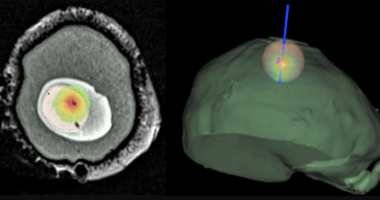

Thérapie et Chirurgie

Le laser est devenu aujourd’hui un outil irremplaçable pour la médecine moderne. Si les premières applications cliniques ont concerné les domaines de l'ophtalmologie et la dermatologie, les champs thérapeutiques exploitant des lasers se sont entre-temps considérablement élargis. Le laser est devenu ainsi un outil précieux et indispensable pour le soin et l... -